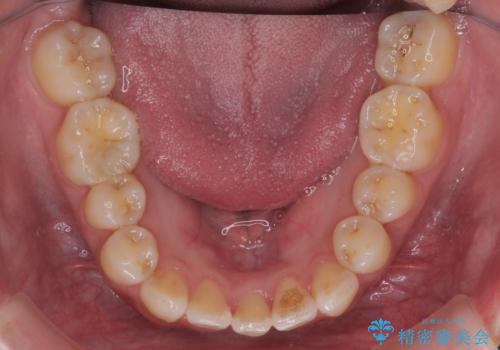

- 前歯のがたつき、受け口を主訴に来院。

上の前歯が二本裏側に入っていました。(反対咬合といいます)

上はワイヤー部分矯正、下はインビザライン(マウスピース)で部分矯正を行いました。

下の前歯を内側に入れる為、一本抜歯しています。

全体矯正で治そうとすると非抜歯ですとだいぶ口元が前に突出するのに加え、下の前歯が入りきらない可能性がありました。上下左右4本抜歯となるため、それを回避するのに下の前歯を1本抜歯して、下の前歯を確実に内側に入れています。